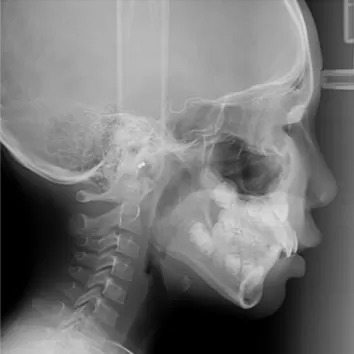

X-rays before treatment

[Panoramic Radiography/Lateral Cephalogram]